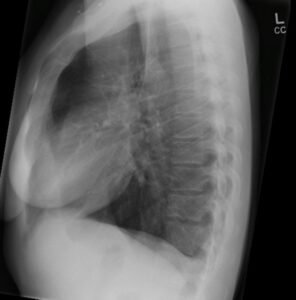

Chest X-Ray of a Pregnant Asthmatic Patient

• Clinical Examination: BP-135/74 RR-22/min HR-120/min T-36.3 O2 sats- 93% on air , she was dyspnoeic and appeared unwell.

A 31-year-old patient presented with a one-day history of sudden onset of the left shoulder pain and shortness of breath. She has no history of trauma or fall. She has no fever, cough, no palpitations or syncope, and no calf swelling or tenderness. The patient has experienced persistent nausea, vomiting and had had poor oral intake with normal bowel motions. The pregnancy test done the previous week is positive and the patient estimates that she was 6 weeks pregnant. She had a background history of Asthma. She use Salbutamol and Fostair inhalers and smoke 10 cigarettes a day.

right sided pleural effusion